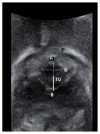

Methods: 76 women with SUI with or without pelvic organ prolapse after sling surgery. They underwent sling surgery alone (S group, n=36) or concomitant TVM (M group, n=40). All patients underwent urinalysis, pelvic examinations, urodynamic study, 3D perineal ultrasonography, and personal interviews before and 1 year after surgery. The urethral area was calculated from the axial plane of perineal ultrasonography by multiplying π by the long and short axes of the urethral lumen.

Results: The axial area of the middle and distal urethra during straining was significantly smaller than at rest in both groups (P<0.001). In addition, the length of the short axis of the proximal urethra was significantly shorter in those undergoing sling surgery alone during straining compared with those undergoing concomitant sling and mesh surgery (P<0.001).